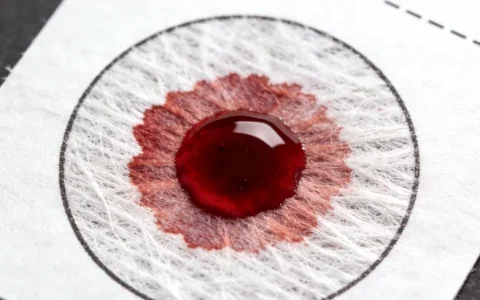

检测方法的差异直接关系到结果的准确性。有些机构用的是抗体检测,只能判断是否感染过病毒;而基因检测(PCR方法)能直接检测病毒DNA,灵敏度高,特别适合备孕和孕期监测。咨询者在选择时一定要问清楚用的是哪种检测方法。